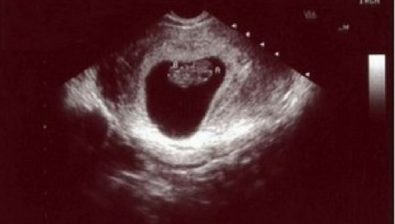

Ultrasound at 9 Weeks

Week nine is a milestone week as your baby has officially graduated from embryo to fetus. Although there is no cap and gown, you and your baby’s progress is to be celebrated nonetheless.

According to the science of it all, there are two main phases for your baby during pregnancy: the embryonic phase and the fetus phase.

During the first phase, your embryo is busy forming major organs. After graduation, your baby (fetus) is all about growing and developing everything started in phase one.